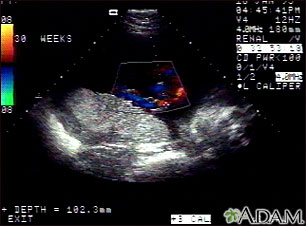

Ultrasonido Doppler normal a color, del cordón umbilical, a las 30 semanas de gestación. El cordón corresponde al área coloreada en el centro de la pantalla y los vasos del mismo están representados por diferentes colores. El cordón umbilical normalmente se compone de tres vasos sanguíneos, a saber, dos arterias y una vena y está conectado a la placenta, la cual está ubicada en la parte central izquierda de la imagen.